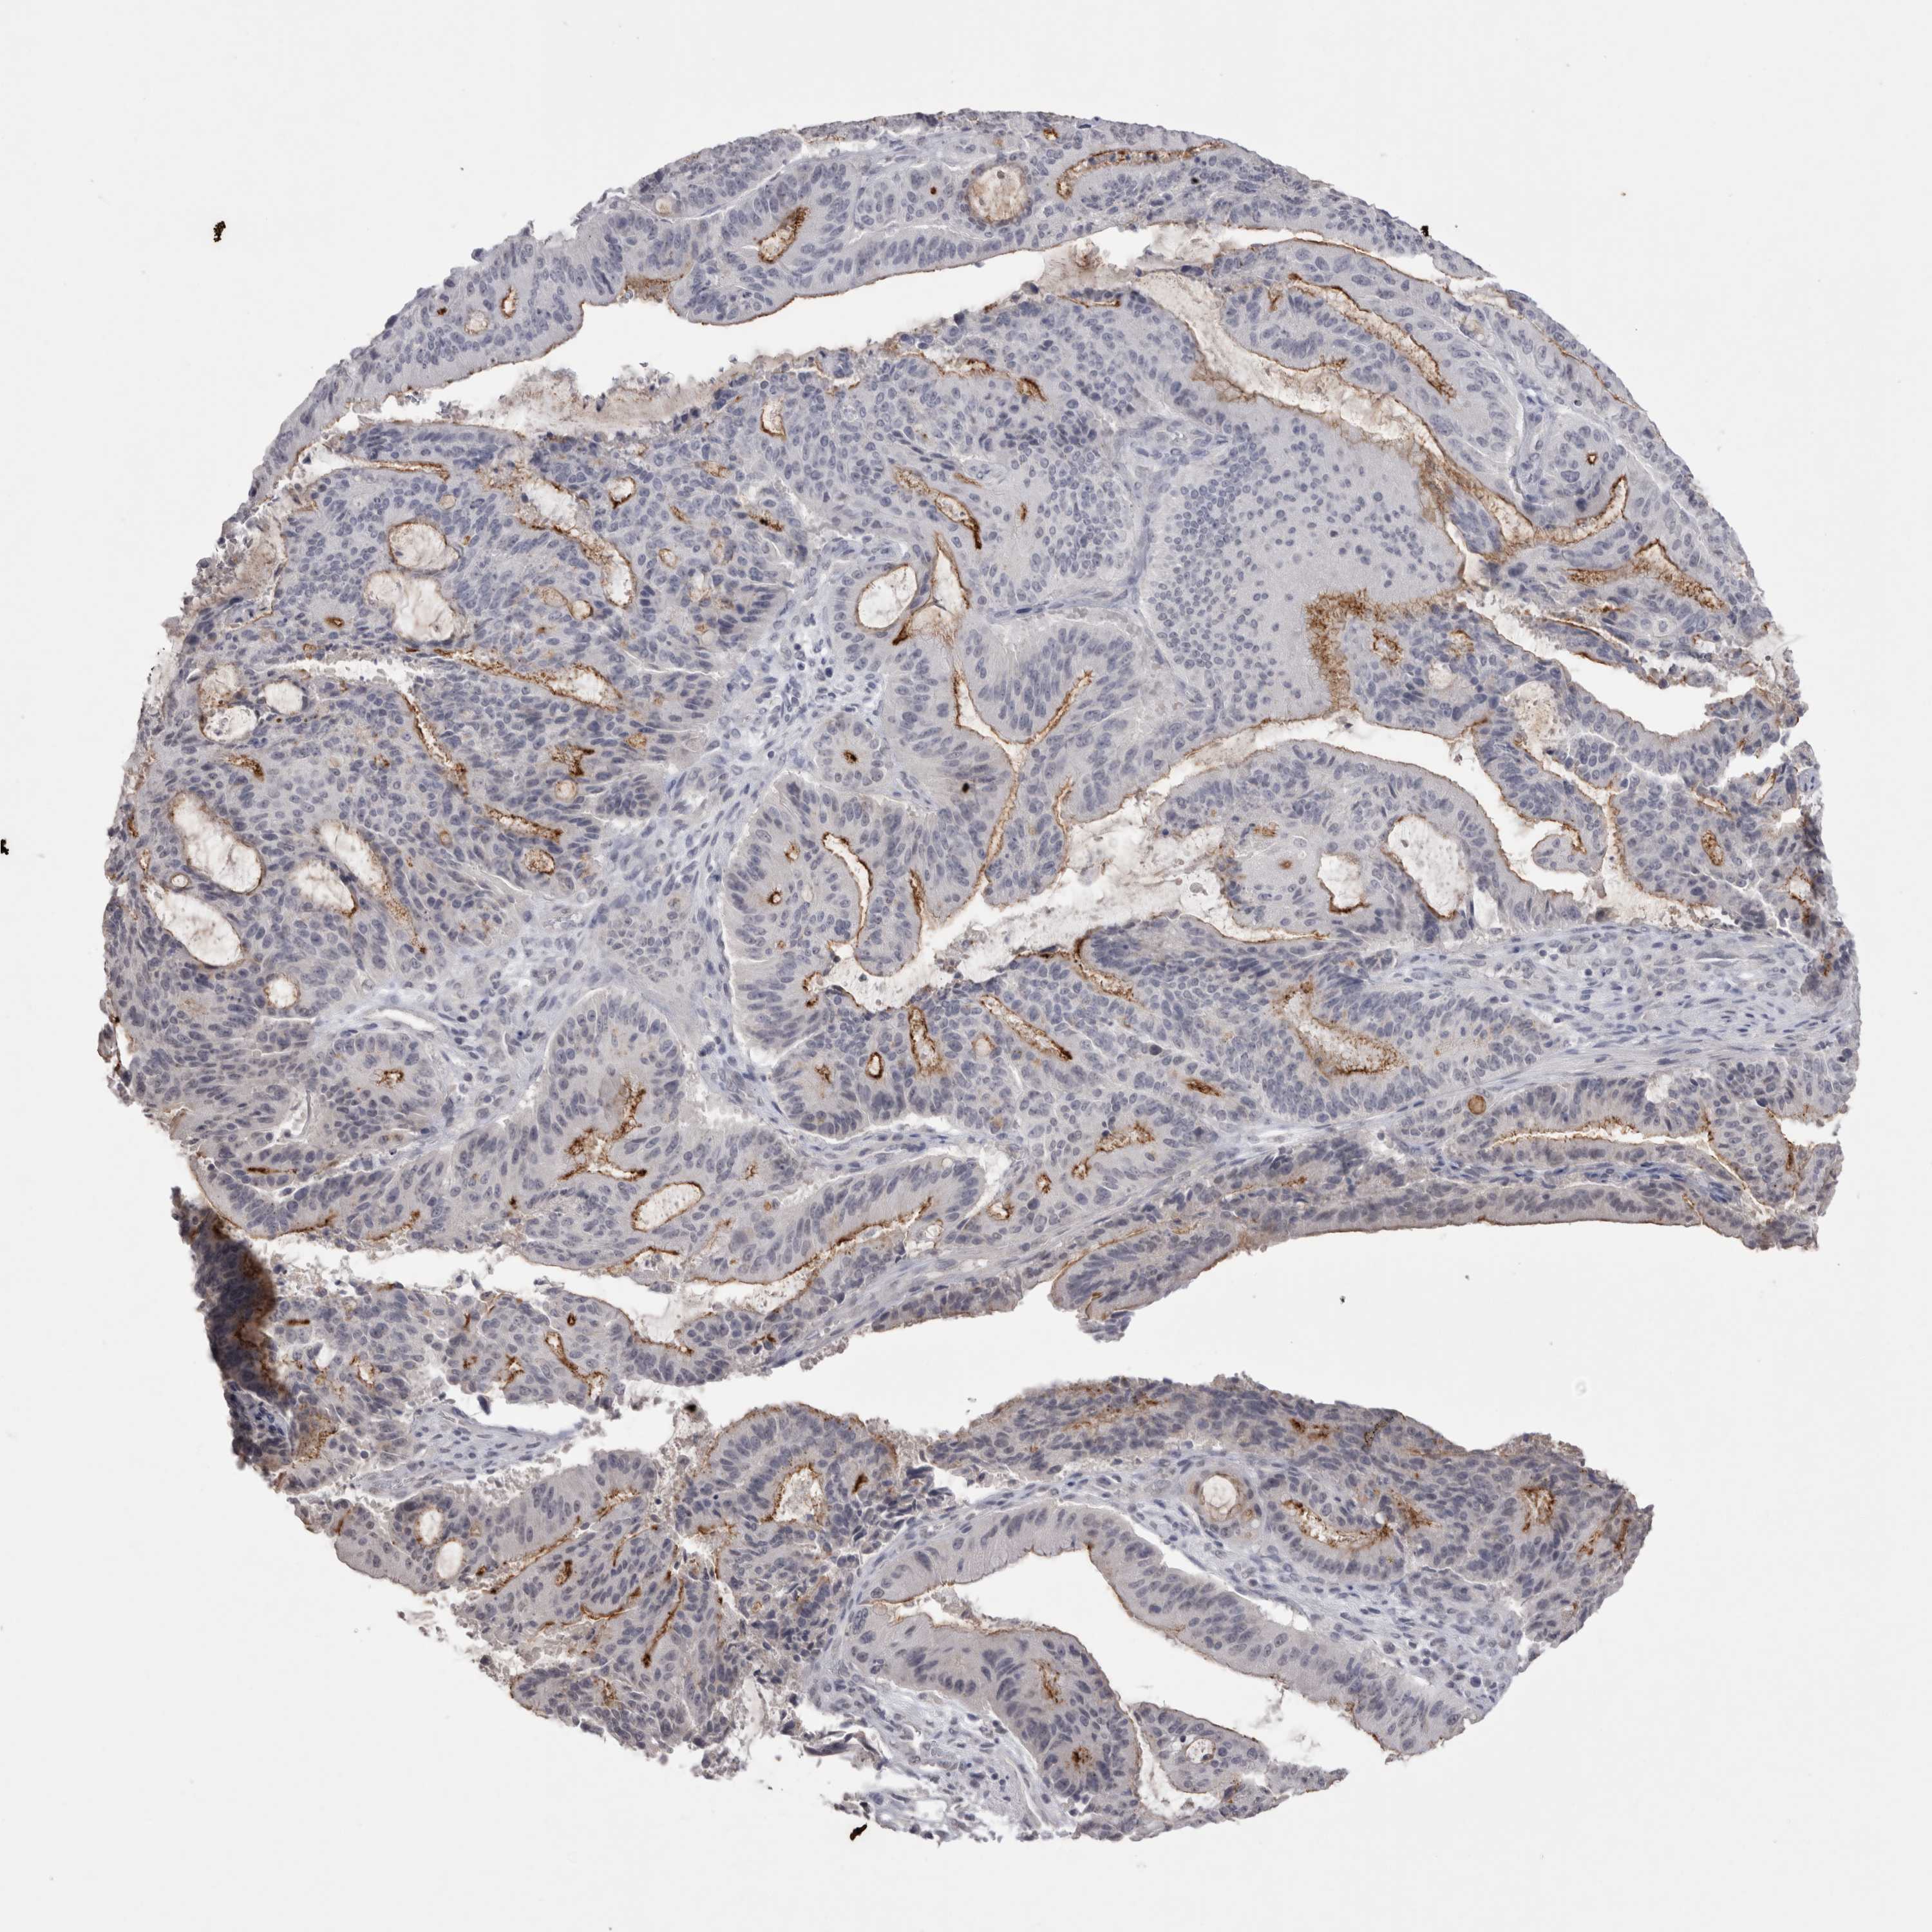

LIVER CANCER - Protein expressioni

A mouse-over function shows sample information and annotation data. Click on an image to view it in a full screen mode. Samples can be filtered based on level of antibody staining by selecting one or several of the following categories: high, medium, low and not detected. The assay and annotation is described here.

Note that samples used for immunohistochemistry by the Human Protein Atlas do not correspond to samples in the TCGA dataset.

Antibody stainingi

Antibody staining in the annotated cell types in the current human tissue is reported as not detected, low, medium, or high, based on conventional immunohistochemistry profiling in selected tissues. This score is based on the combination of the staining intensity and fraction of stained cells.

Each image is clickable and will lead to virtual microscopy that enables deeper exploration of all samples and also displays staining intensity scores, fraction scores and subcellular localization as well as patient and tissue information for each sample.

Antibody HPA037763

Antibody HPA037764

Antibody CAB026170

Staining

Cholangiocarcinoma

Carcinoma, Hepatocellular, NOS